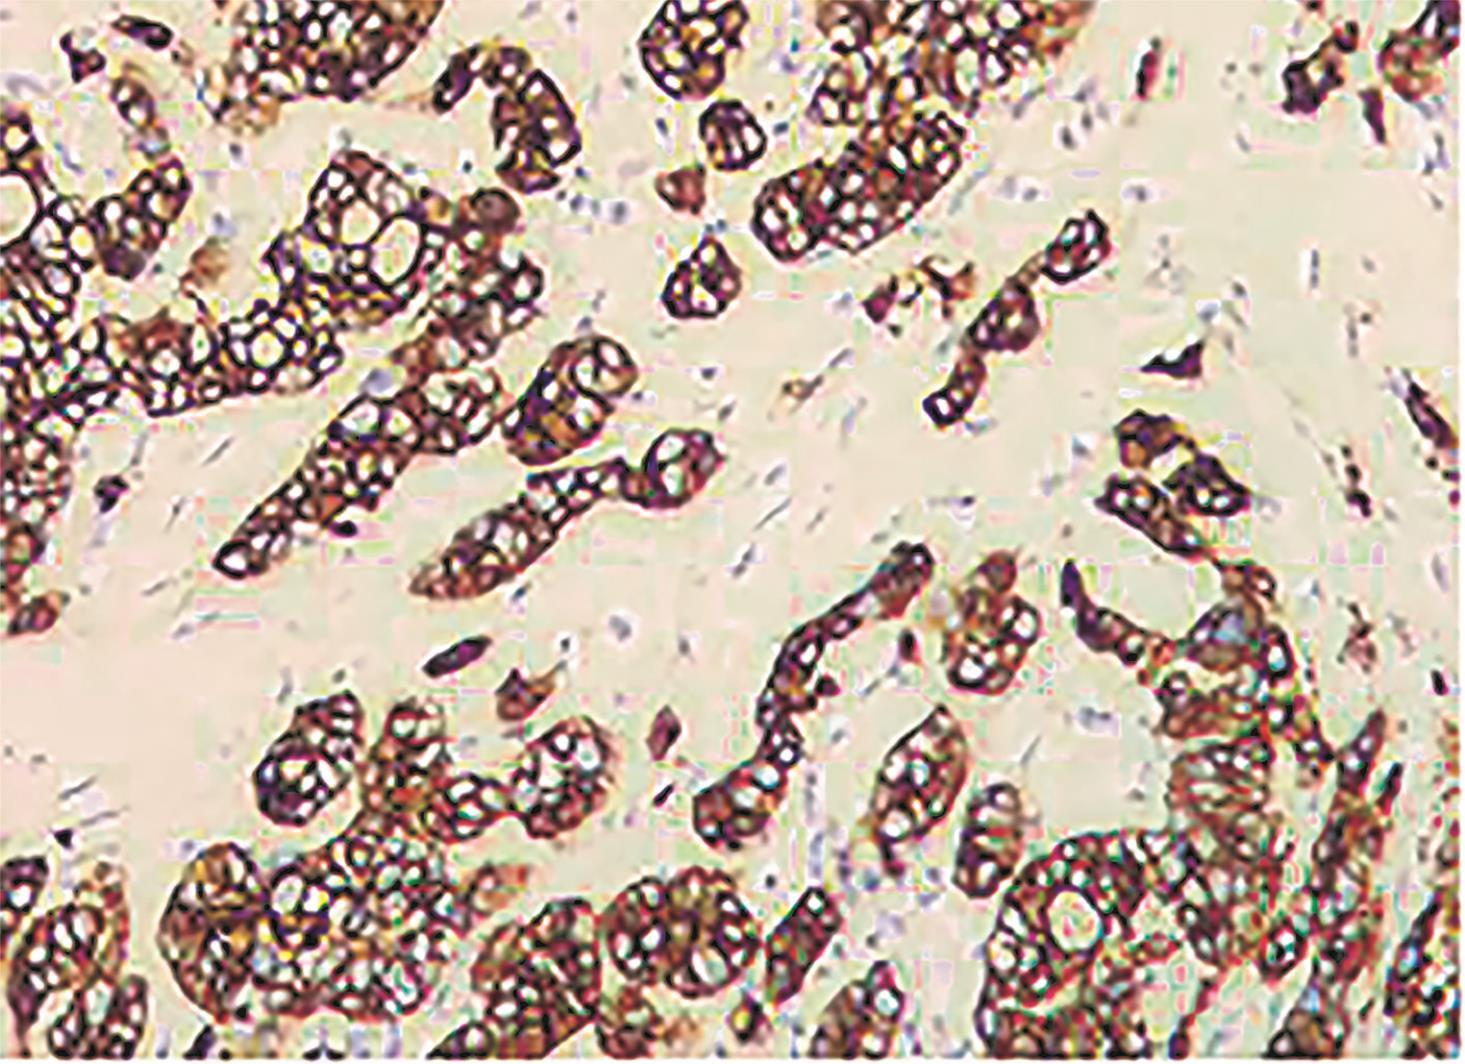

• 胆囊腺癌伴印戒细胞癌1例

摘要: